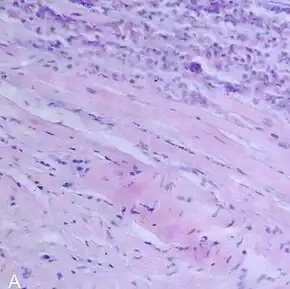

A microscope image of myocarditis at autopsy in a person with acute onset of heart failure

The gold standard is the biopsy of the myocardium, in general done in the setting of angiography. A small tissue sample of the endocardium and myocardium is taken and investigated. The cause for the myocarditis can be only diagnosed by a biopsy. Endomyocardial biopsy samples are assessed for histopathology (how the tissue looks like under the microscope: myocardial interstitium may show abundant edema and inflammatory infiltrate, rich in lymphocytes and macrophages. Focal destruction of myocytes explains the myocardial pump failure.[11] In addition samples may be assessed with immunohistochemistry to determine which types of immune cells are involved in the reaction and how they are distributed. Furthermore, PCR and/or RT-PCR may be performed to identify particular viruses. Finally, further diagnostic methods like microRNA assays and gene-expression profile may be performed.